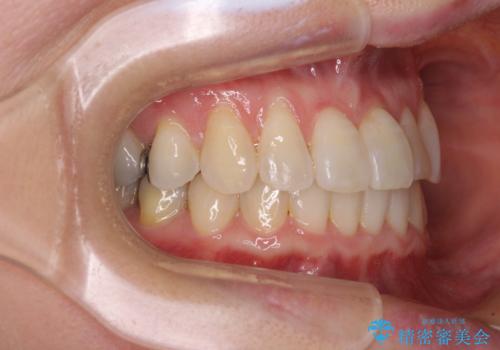

前歯のクロスバイト インビザライン矯正で改善

- むし歯治療を契機に、長年気にしていた前歯のクロスバイトの改善を希望された患者様です。

汚れが溜まりやすく、歯ぎしりがうまくできないため、インビザラインを用いて矯正治療を行うこととしました。

インビザラインによる前歯のクロスバイトの改善は、治療期間中に前歯でしか咬めない時期が続いたり、歯肉退縮や歯髄壊死のリスクが高まったりと、治療中にトラブルを抱えることがあります。

特に上顎側切歯(真ん中から2番目の歯)が舌側に引っ込んでいるケースは、インビザラインでは改善しきれないことがあると言われています。